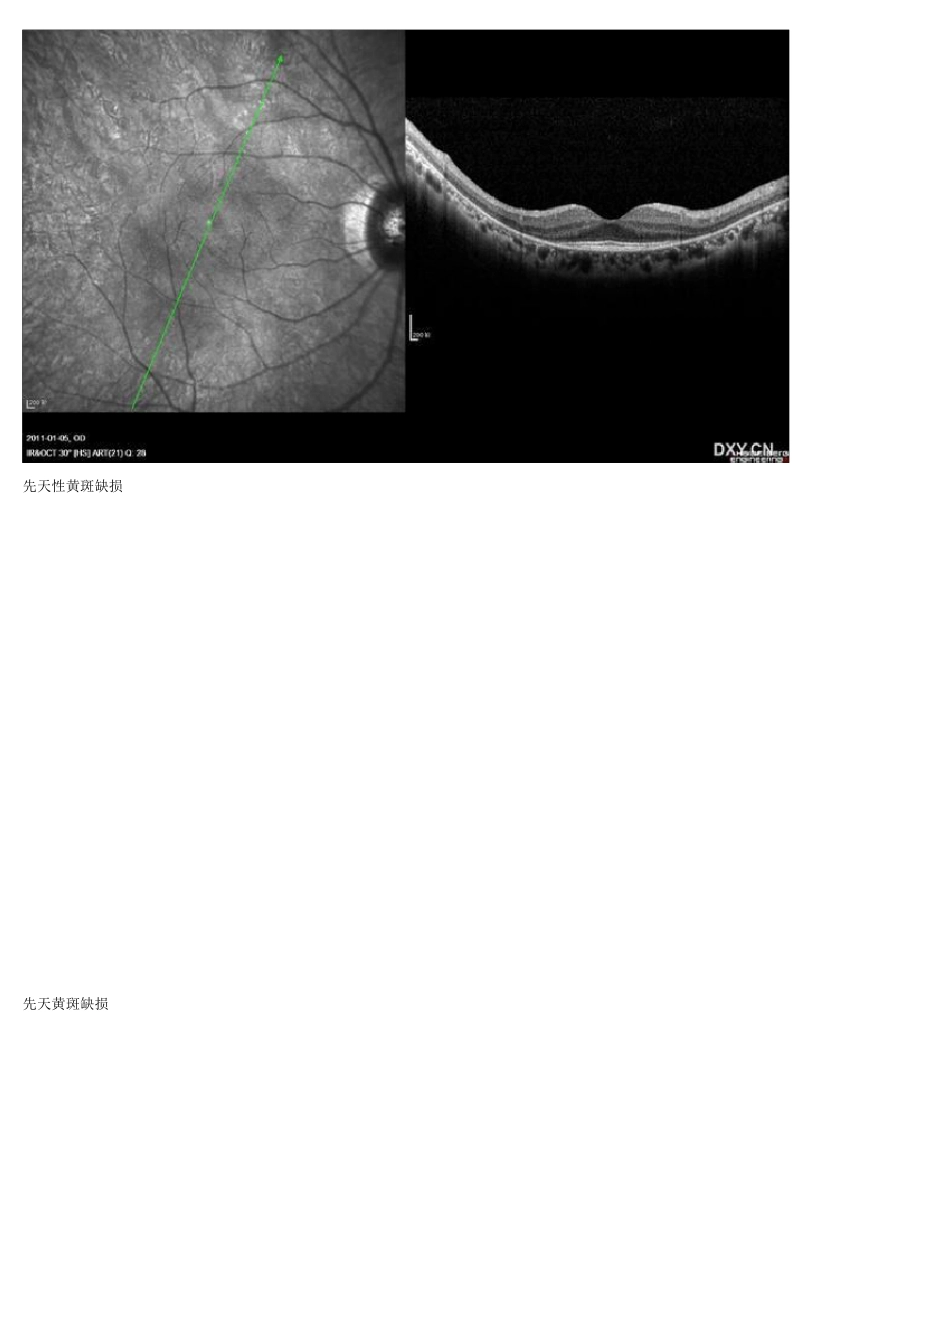

OCT视网膜10 层结构 视网膜色素变性: 除黄斑区仅余的IS/OS反射光带外,余未见IS/OS反射光带。 先天性黄斑缺损 先天黄斑缺损 假性黄斑裂孔 视网膜前膜 黄斑中心凹失去正常轮廓,变陡峭,中心凹视网膜厚度正常, 中心凹周围网膜前见一强反射光带,与视网膜粘连紧密。 假性黄斑裂孔 视网膜前膜 黄斑中心凹失去正常轮廓,变陡峭,中心凹视网膜厚度正常, 中心凹周围网膜前见一强反射光带,与视网膜粘连紧密。 1、 正常视盘凹陷位置 2、视盘小凹 3、脉络膜囊样暗区 玻璃膜疣 OCT示视网膜色素上皮隆起,下方为轻中度反射,与脉络膜反射无区别, 从隆起的视网膜色素上皮延伸到脉络膜。 视网膜前出血: OCT示神经上皮层及其下反射光带并迅速衰减。局部反射光带被遮蔽。 视 网 膜 劈 裂 OCT图 玻 璃 膜 疣 肉 眼 看 : 玻 璃 膜 疣 形 态 比 较 规 则 , 硬 性 渗 出 形 态 欠 规 则 还 可 以 借 助 OCT, 病 灶 的 深 度 不 一 样 。 玻 璃 膜 疣 一 般 都 是 比 较 圆 滑 , 而 硬 性 渗 出 比 较 有 棱 角 , 就 像 一 个 是 鹅 卵 石 , 一 个 是 是 山 上 的 岩 石 , 软 性 渗 出 , 现 在 也 不 这 样 叫 了 , 都 叫 棉 絮 般 ,颜 色 就 好 区 分 了 , 一 般 都 是 白 色 或 乳 白 色 , 边 界 不 是 很 清 楚 , 高 视 远 望 眼 病 讲 坛 , 同 仁 医 院 彭 晓 燕 教 授 讲 : 二 者 都 是 黄 色 的 , 多 半 位 于 后 极 部 , 但 二 者 来 源 不 同 、 位 置 不 同 。 我 们 所 说 的 硬 性 渗 出 都 是 来 自 视网 膜 , 边 界 相 对 锐 利 , 而 玻 璃 膜 疣 位 于 视 网 膜 下 、 被 视 网 膜 色 素 上 皮 覆 盖 , 边 界 就 相 对 模 糊 , 轮 廓 相 对 圆 润 。 前者 就 像 “石 头山 ”, 后 者 可 比 作“大土包”, 这 样 区 分 二 者 边 界 和形 态 的 不 同 。 另外, 从形 成机制来 说 , 在 硬 性 渗 出 的 周围通常有 异常血管(微血管瘤或 血管壁改变)。 从OCT检查结果 上 也 能 根 据 病 变位 置 做 出 区 分 。 硬性渗出和玻璃膜疣在FFA 上对照眼底彩照可以鉴别。 硬性渗出...